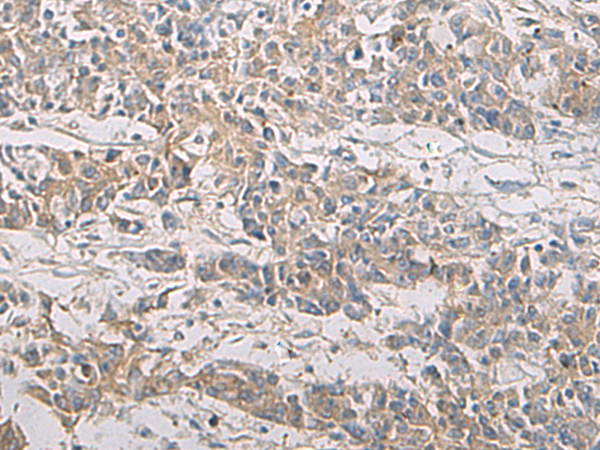

IHC (Immunohistochemistry)

(Immunohistochemistry of paraffin-embedded Human colorectal cancer tissue using PA2G4 Polyclonal Antibody at dilution of 1:60(×200))